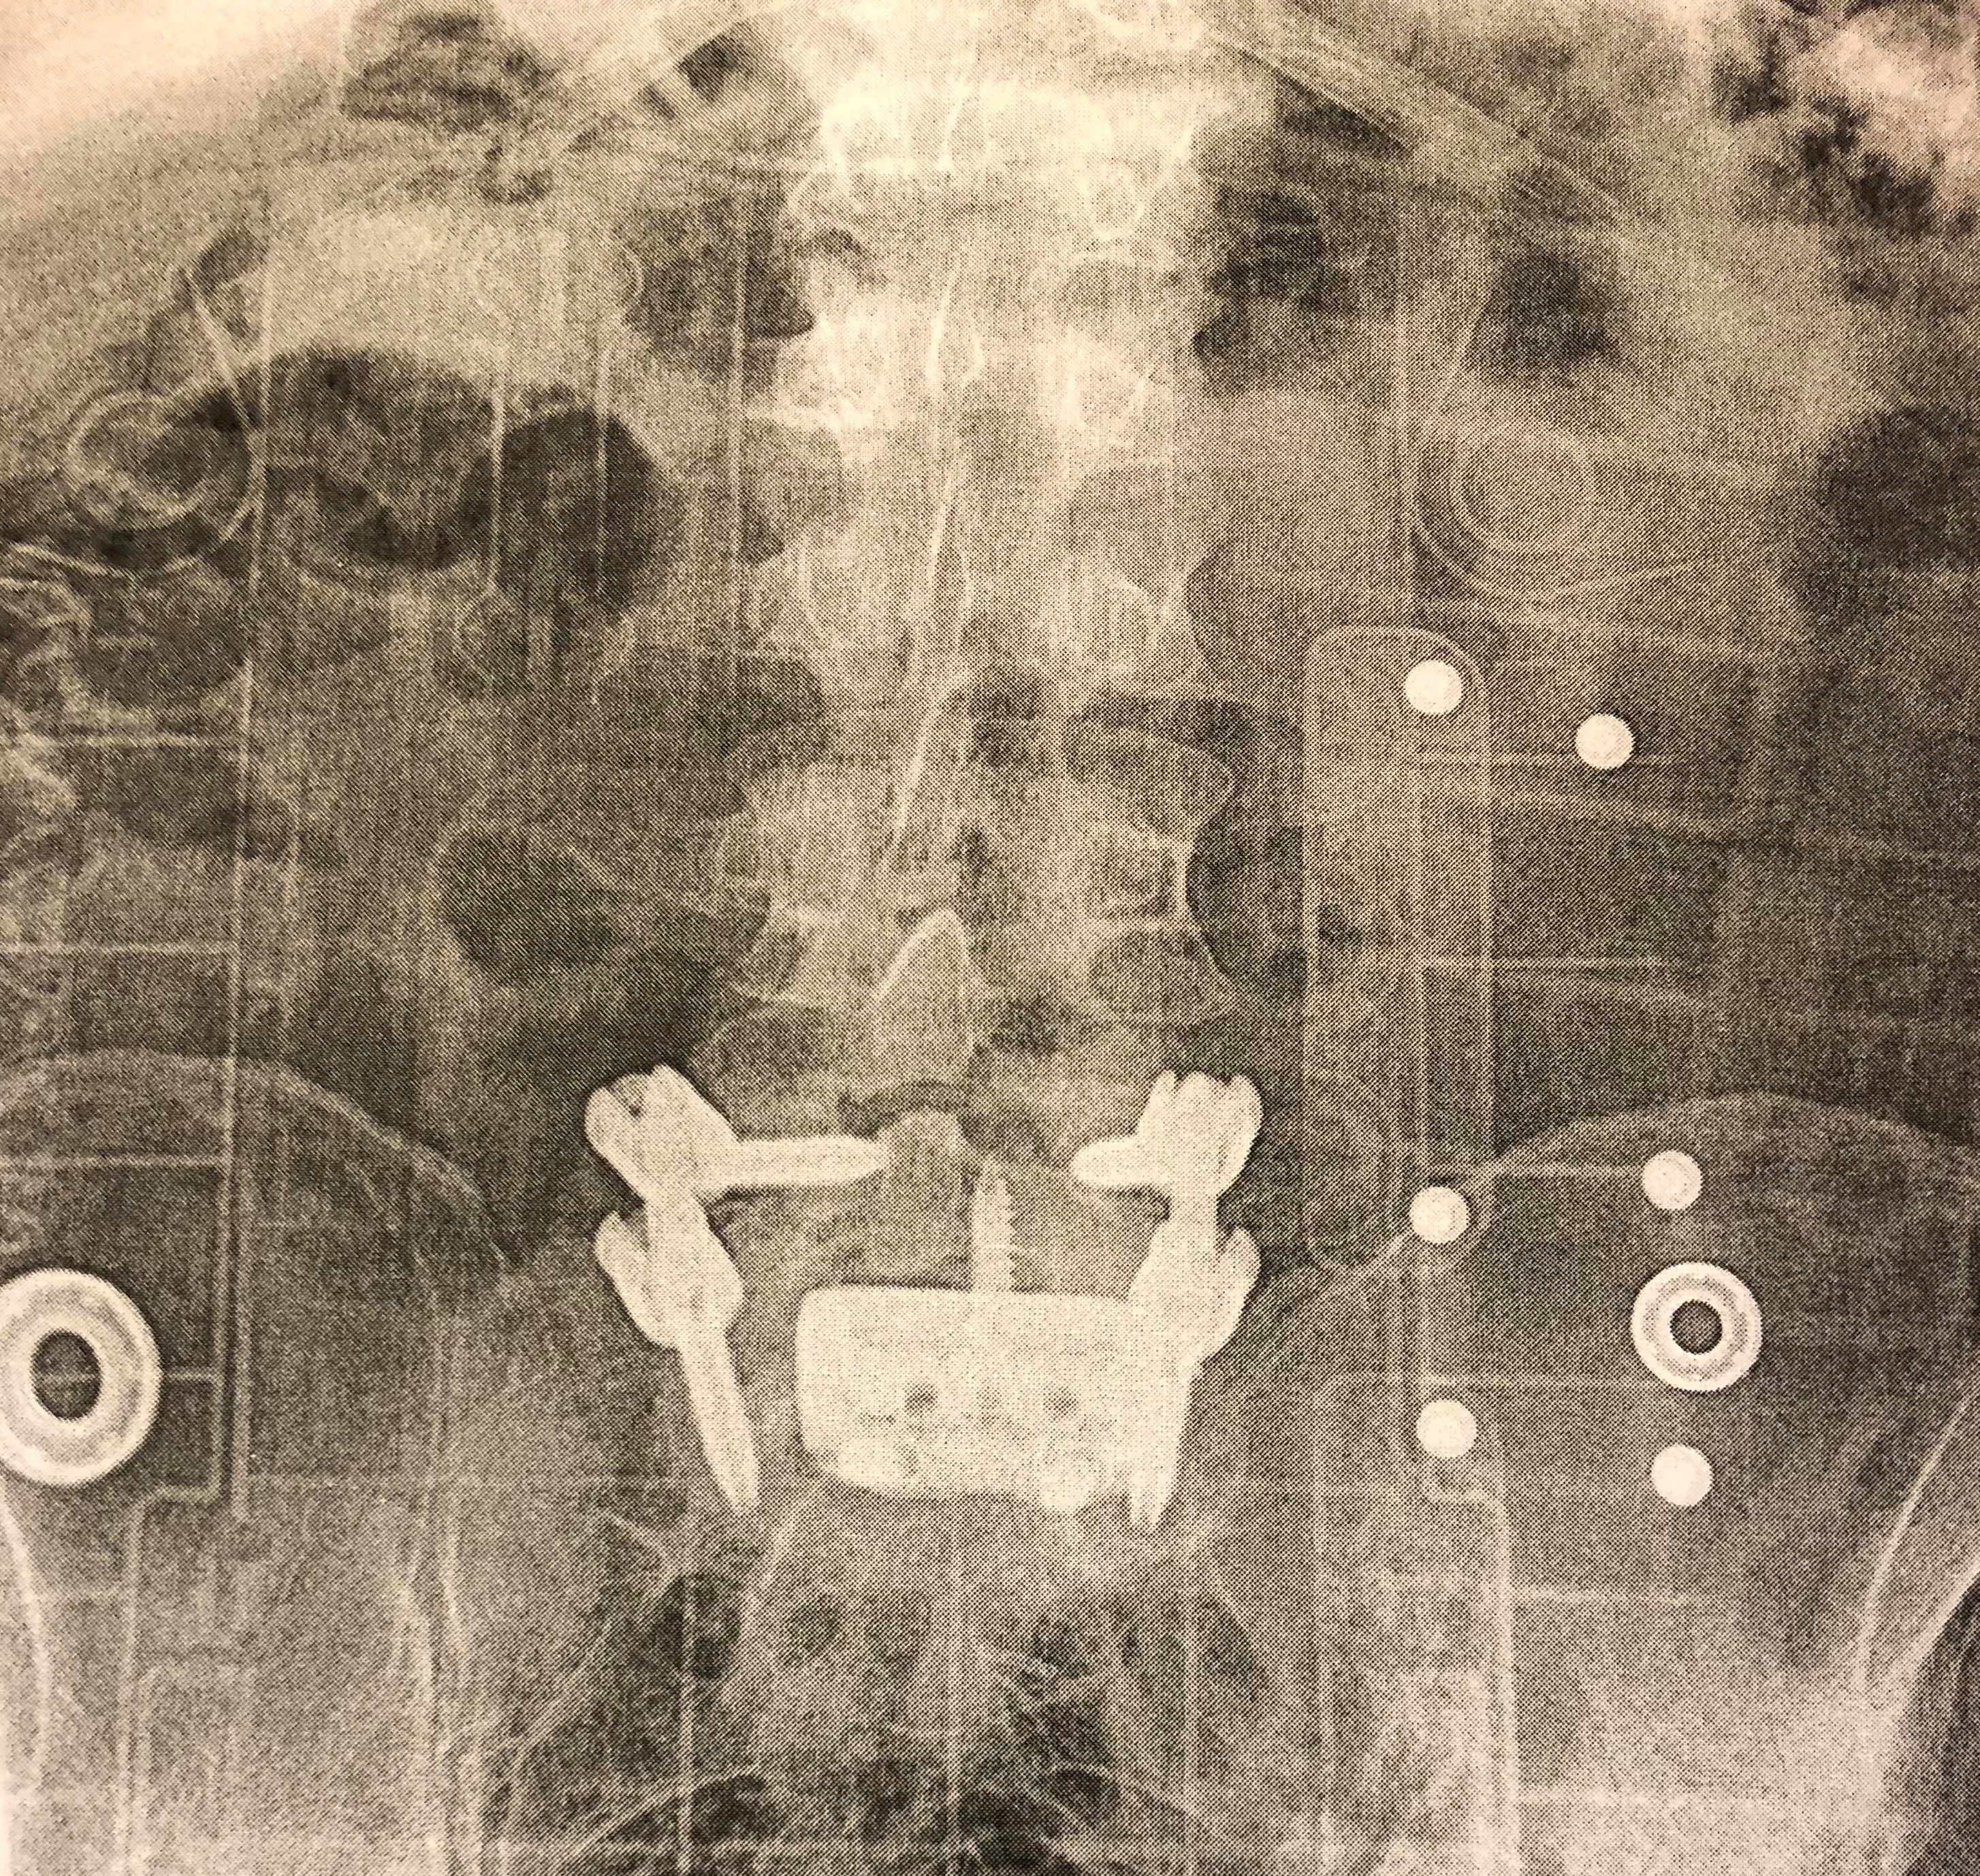

IMG_0305.jpeg